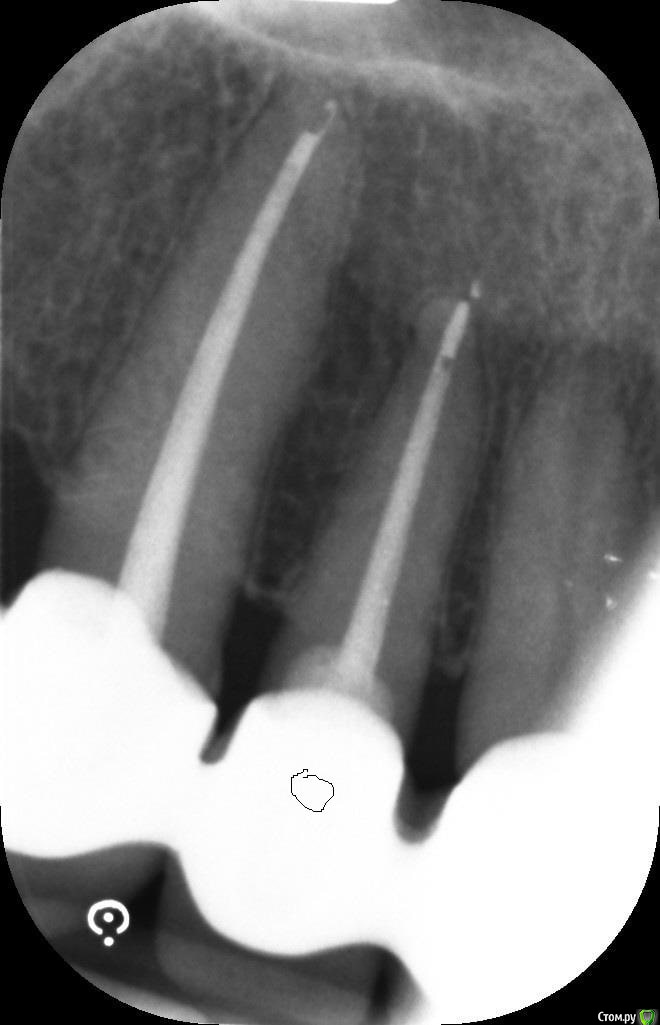

ellenchik Опубликовано 14 января, 2020 Поделиться Опубликовано 14 января, 2020 Уважаемые Доктора, очень прошу Вашего совета по рентг. снимку. Болит зуб высоко вверху над десной. (отмечен кружочком) Боль усиливается при нажатии точки между этим, с запломбированным каналом зубом и зубом без пломбировки рядом. Вопросы1). Воспаление в корнях?2). Резекция корня?3). Курс антибиотиков?Ну очень важно Ваше мнение! Что можно сказать по снимку?Просьба к модераторам - не закрывать ветку (т.к. я задавала этот вопрос в "Терапии" . Но никто не ответил) Наверно это всё же хирургическая тема.С уважением Елена Ссылка на комментарий

hogsmeed Опубликовано 14 января, 2020 Поделиться Опубликовано 14 января, 2020 Выглядит все хорошо, патологии не видноНПВС снимают боль? Ссылка на комментарий

Zlata-doctor Опубликовано 15 января, 2020 Поделиться Опубликовано 15 января, 2020 когда делался этот снимок?Я считаю, что пока о резекции говорить рано, на представленном снимке имеются некоторые признаки переапикальной патологии ( прерывается периодонтальная щель в области верхушки корня зуба), но четко процесс не визуализируется. Сделайте , как вам здесь посоветовали, КТ). Но если уж придется делать, то ( мое мнение) ЛУЧШЕ сделать у специалиста-эндодонта, который владеет также эндодонтической хирургией ( апикальной хирургией). Ссылка на комментарий

ellenchik Опубликовано 15 января, 2020 Автор Поделиться Опубликовано 15 января, 2020 когда делался этот снимок?Я считаю, что пока о резекции говорить рано, на представленном снимке имеются некоторые признаки переапикальной патологии ( прерывается периодонтальная щель в области верхушки корня зуба), но четко процесс не визуализируется. Сделайте , как вам здесь посоветовали, КТ). Но если уж придется делать, то ( мое мнение) ЛУЧШЕ сделать у специалиста-эндодонта, который владеет также эндодонтической хирургией ( апикальной хирургией). Снимок свежий-08.01.2020 Врач прописал пока Амоксиклав на 5 дней. КТ постараюсь на след. неделе сделать. Большое спасибо всем Докторам за ответы! 1 Ссылка на комментарий